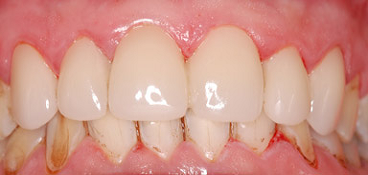

Cas 2 : 4 incisives latérales et 2 canines

Un brossage agressif et le tabac sont à l’origine du désordre dentaire